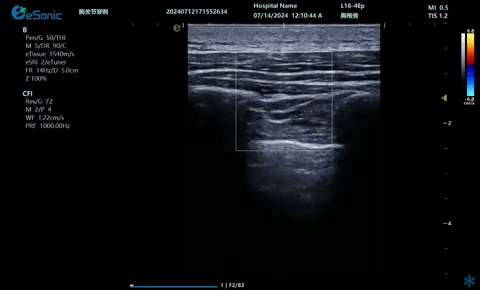

超声引导下蝶颚神经节阻滞术

大雁征-上颌动脉切面

疼痛康复领域中的肌骨超声应用,旨在实现对肌肉、肌腱、韧带、关节、神经、血管、筋膜、滑膜、滑囊、骨膜等组织结构的精确诊断评估。由于超声高频探头对上述机体组织的细微结构具有优异的分辨率,因此能够更为明确地评估这些组织的损伤和炎症状态。同时,超声设备的实时动态评估能力,使得对运动中的相关疾患也能进行准确的评估,这是其他诊断设备所不具备的优势。在康复治疗过程中,肌骨超声还用于介入穿刺治疗,如外周神经阻滞(PNB)、小关节注射、肌筋膜松解术、封闭、小针刀、冲击波治疗等。在超声引导下,这些治疗操作实现了可视化,从而真正意义上实现了精准医疗。以PNB为例,作为一种局部用药方式,其对患者全身干扰小,药物副作用少,且费用较低,因此仍然是临床治疗疼痛的主要方式之一近年来,超声技术在临床康复领域的应用日益凸显其优势。相较于传统的盲穿技术,超声引导下的PNB能够直观显示穿刺和注药过程,无需患者表达异感,避免了反复穿刺给患者带来的痛苦。这种技术显著提高了外周神经阻滞、静脉穿刺的成功率、精确性和安全性,同时减少了不良反应和并发症的发生,为患者带来了福音也相信在不久的将来,eHertz系列产品将会在全球医疗市场上掀起一场技术革新的风暴,让更多的人受益于我国医疗技术的进步。